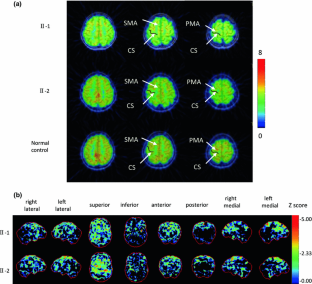

SPG3A-linked hereditary spastic paraplegia (HSP) is a rare autosomal dominant motor disorder caused by a mutation in the SPG3A gene, and is characterized by progressive motor weakness and spasticity in the lower limbs, without any other neurological abnormalities. SPG3A-linked HSP caused by a R239C mutation has been reported to present a pure phenotype confined to impairment of the corticospinal tract. However, there is still a debate about the etiology of this motor deficit with regard to whether it is peripheral or central. We herein report two patients who were heterozygous for a R239C mutation in the SPG3A gene. Two middle-aged Japanese sisters had been suffering from a pure phenotype of HSP since their childhood. Both patients had a significant decrease in glucose metabolism in the frontal cortex medially and dorsolaterally in a [18F]-fluorodeoxyglucose (FDG) positron emission photography (PET) study and low scores on the Frontal Assessment Battery. A real-time PCR analysis in normal subjects showed the frontal cortex to be the major location where SPG3A mRNA is expressed. The present finding that the frontal glucose hypometabolism was associated with frontal cognitive impairment indicates that widespread neuropathology associated with mutations in the SPG3A gene may be present more centrally than previously assumed.